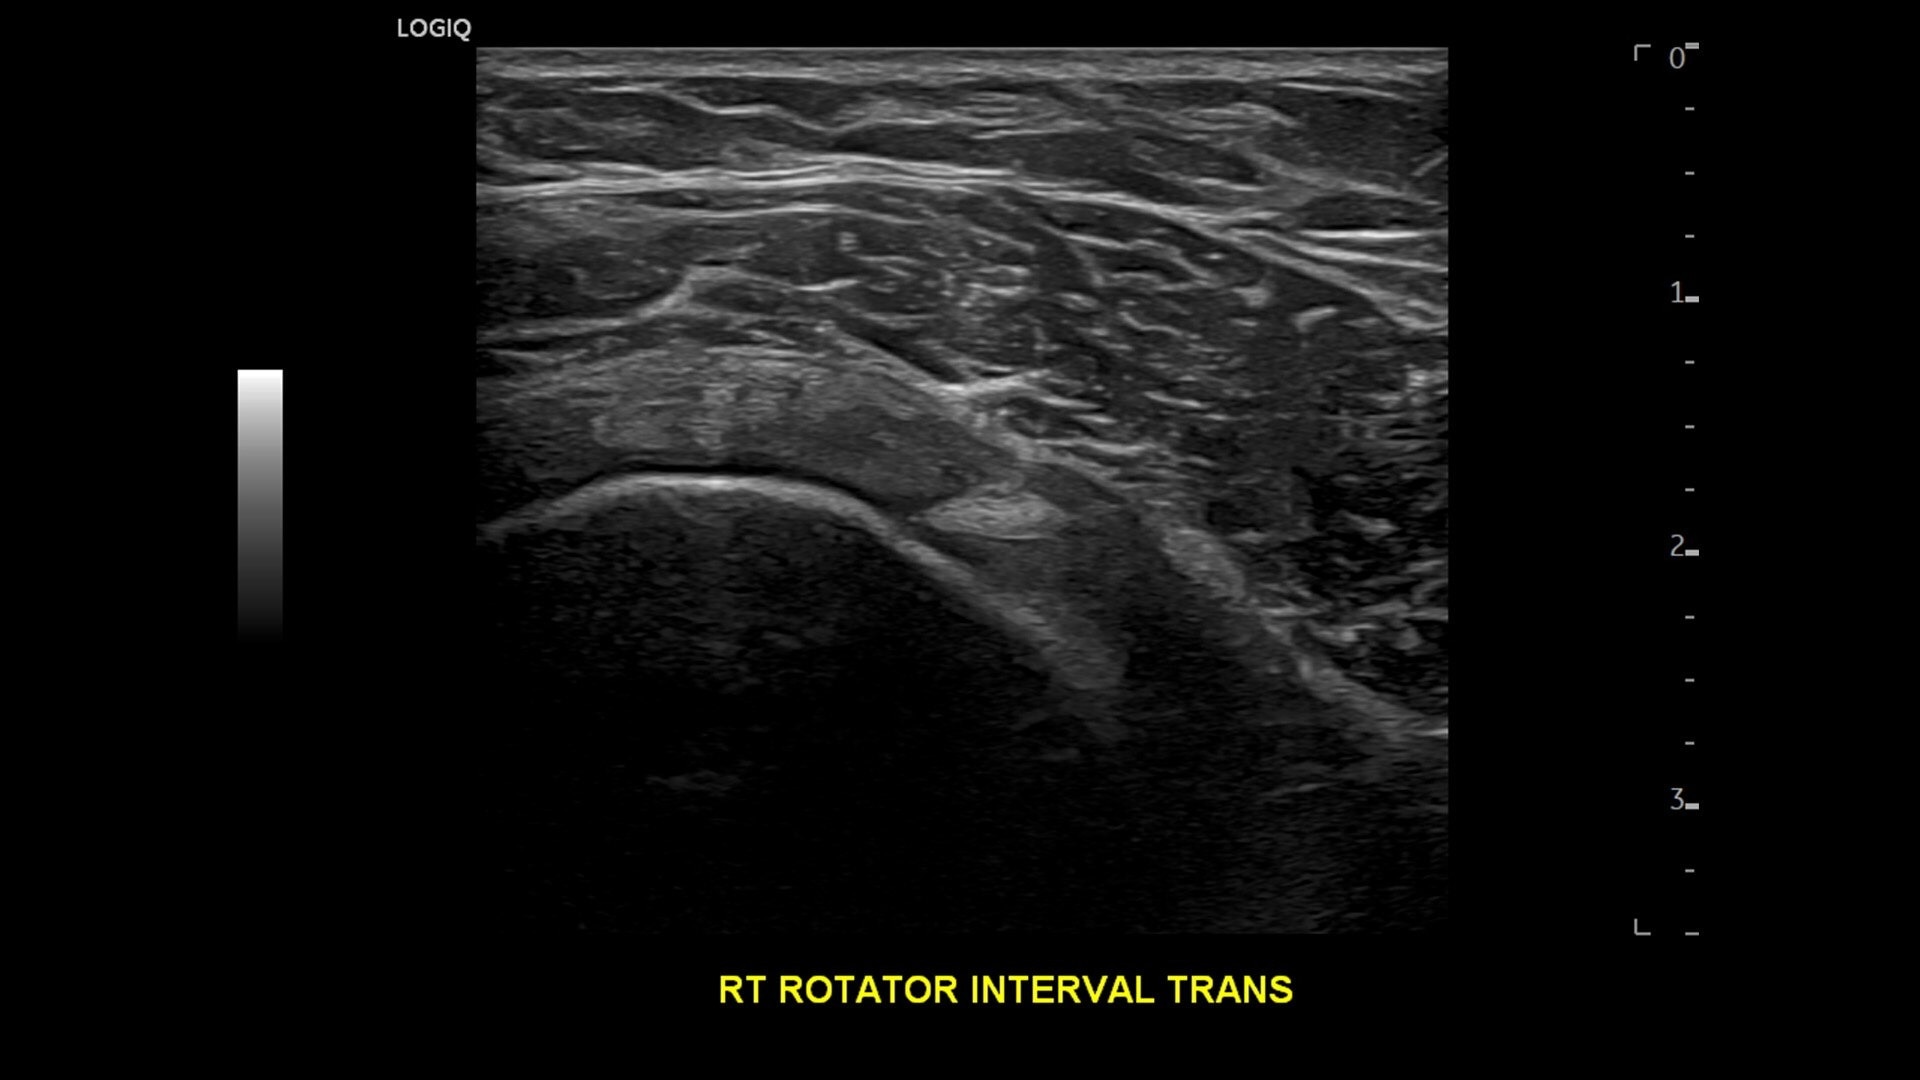

With versatility and AI-powered decision support, LOGIQ Totus is the trusted companion for busy practices with a wide range of patients across a variety of care areas.

• cSound™ Architecture delivers exceptional clarity and resolution from near field to depth—with all pixels in focus

• Next‑level specialty and multi‑purpose probes—plus Pulsed Wave Doppler now available on the wireless Vscan Air™ CL —expand your clinical flexibility.

• Advanced flow modes give you the flexibility, from large vessels to fine microvascular detail, to visualize blood flow with precision